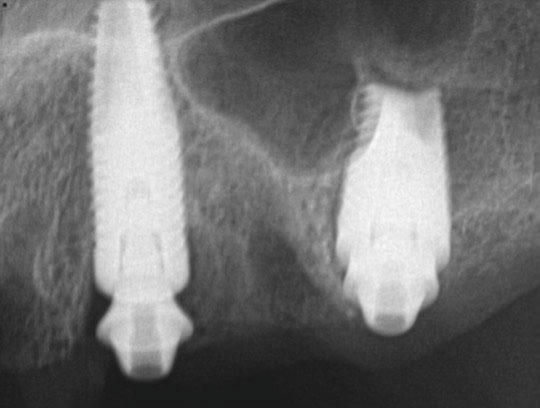

Fig 22. Postoperative periapical x-rays on the day of surgery demonstrating the provisional restoration with ti-bases fully seated to multi-unit abutments and ideal immediate implant placement.

Figure 22

Fig 41. Postoperative periapical x-rays on the day of surgery demonstrating ideal immediate implant placement in bone.

Figure 41

Fig 42. Postoperative periapical x-rays on the day of surgery demonstrating ideal immediate implant placement in bone.

Figure 42

When the patient presented for insertion of the final prosthesis, the provisional prosthesis was removed and the final prosthesis was inserted onto the multi-unit abutments. One multi-unit screw was placed with hand-tightening in the most distal position on the patient's left side. Periapical radiographs were taken paralleling the multi-unit abutment to the final prosthesis joint to confirm complete passive seating of the restoration. After confirming that the restoration sat passively and completely on the multi-unit abutments, the remainder of the multi-unit screws were inserted, and all were torqued to 20 Ncm using a torque driver. The occlusion was then evaluated; this included checking centric contact points as well as for lateral excursive and protrusive guidance.

Postoperative x-rays documented the full seating of the prosthesis on the multi-unit abutments (Figure 21 and Figure 22). The patient returned at 1 week postoperatively for a follow-up visit and to review home care. She remarked that the restoration was comfortable and that she was free of discomfort and extremely pleased with the makeover she received in one day.